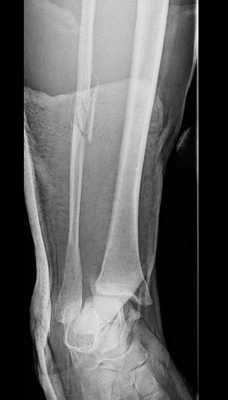

Клинический пример лечения разрыва дистального межберцового синдесмоза в нашей клинике.

Пациент Д.27 лет, травма в результате неудачного приземления после прыжка старзанки на мелководье. Стопа ушла кнаружи относительно фиксированной голени. Произошёл перелом малоберцовой кости в средней трети с разрывом всех компонентов дистального межберцового синдесмоза и отрывной перелом внутренней лодыжки.

Данный тип переломов лодыжек считается очень тяжёлым и относится к категории 44С2 по классификации Ассоциации Остеосинтеза. Казалось бы, сломаны всего 2 кости, да и переломы по своей морфологии не особо и тяжёлые, почему же данный тип переломов лодыжек считается крайне тяжёлым?

Всё дело в повреждении мягких тканей, прежде всего разрыве всех 4 компонентов дистального межберцового синдесмоза - передней и задней нижних межберцовых связок, межкостной связки и межкостной мембраны. Вместе с отрывом медиальной лодыжки всё это делает перелом абсолютно нестабильным и требует операции в 100% случаев.